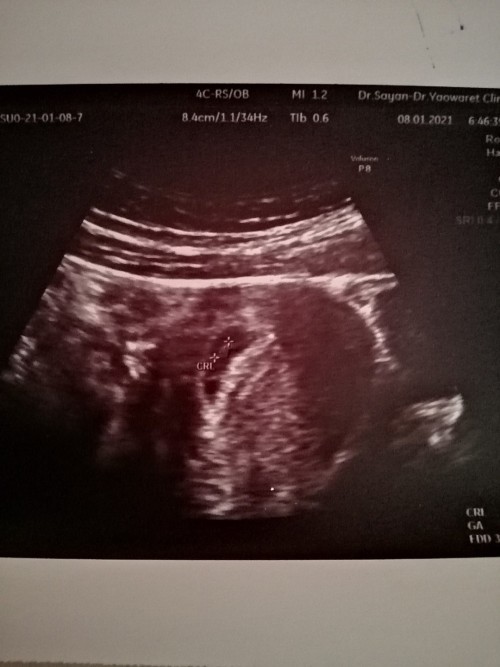

ฝากท้องครั้งแรก8wk(นับจากประจำเดือน) u/sผ่านช่องคลอด เจอถุงตั้งครรภ์แต่ยังไม่เจอตัว หมอบอกว่าจากU/Sแค่6wk อาจจะยังตัวเล็ก นัดอีกทีอาทิตย์หน้า หลังจากที่ไปฝากมา2วัน มีมูกสีน้ำตาลติดกกน. ทุกครั้งที่เข้าห้องน้ำเลยค่ะ แต่ไม่มีปวดท้อง ตอนนี้กลัวมากเลย 😢 มีโอกาสปกติอยู่มั้ยคะ

บ้านนี้ซาวช่องคลอดกว่าจะเจอน้องตัวเล็กมากคะ

ซาวด์ตอน6w6d ปัจจุบัน 17wแล้วค่ะ

เพราะอายุครรภ์ถ้านับจาก ปจดวันเเรกของครั้งสุดท้าย ตอนซาวด์ครั้งเเรกต้อง6วีค แต่ตอนนั้นเราซาวด์เราซาวด์ผ่านช่องคลอดครั้งเเรกอายุครรภ์ได้4วีคค่ะ